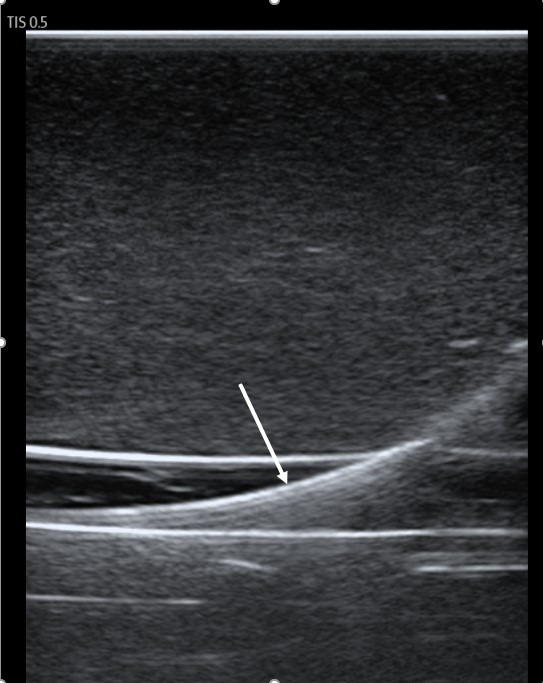

Background: Visualization of the guidewire during internal jugular (IJ) vein catheterization by point of care ultrasound (POCUS) has been recommended for avoiding inadvertent carotid artery dilation. The purpose of this study was to determine the accuracy of POCUS for identifying guidewires inappropriately placed in the carotid artery. Methods: This prospective, observational study involved emergency medicine (EM) residents with varying experience in guidewire visualization. Using an inanimate model, investigators placed guidewires randomly into the carotid artery or IJ vein. Residents, blinded to guidewire location, scanned the model and recorded their findings. The test performance of POCUS for arterially placed guidewires was evaluated through calculation of sensitivity, specificity, negative predictive value (NPV), positive predictive value (PPV), and overall accuracy, using investigator placement as the non-reference standard. Results: Twenty-five residents performed 51 observations. The test performance of POCUS for identifying arterially placed guidewires was sensitivity 95.0% (95%CI = 73.1-99.7%), specificity 96.8% (95%CI = 81.5-99.8%), NPV 96.8% (95%CI = 81.5-99.8%), and PPV 95.0% (95%CI = 73.1-99.7%). The overall accuracy was 96.1% (95%CI = 86.8-98.9%). Residents reported being very confident in their findings in 88.2% of all observations (95%CI = 76.6-94.5%), somewhat confident in 9.8% (95%CI = 4.3-21.0%), and not very confident in 2.0% (95%CI = 0.4-10.3%). No errors occurred among upper-level residents (post-graduate years 2-3) or those reporting >5 prior wire visualizations in live patients. Conclusions: This study is the first to demonstrate that physicians can easily identify misplaced guidewires located in the carotid artery with a high degree of accuracy using POCUS. We recommend routine scanning of the IJ vein and carotid artery prior to vessel dilation to reduce the likelihood of carotid artery injury.

Abstract Image